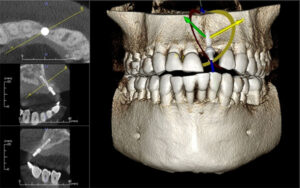

انواع تصویر برداری در ایمپلنت

معمولا در جلسه ی اول مراجعه، دندانپزشک رادیوگرافی مخصوصی را برای شما تجویز می کند.

اولین گرافی جهت بررسی وضعیت کلی دندان ها و یک شمای کلی از ناحیه ی بی دندانی و ارتباط آن با سایر بخش ها و نواحی آناتومیک ،تصویربرداری پانورامیک که به آن OPGهم می گویند می باشد.

این نوع تصویربرداری یک نمای دو بعدی از وضعیت دندان ها و فک شما در اختیار دندانپزشک قرار می دهد.

اما جهت شروع درمان جراحی ایمپلنت کافی نمی باشد.معمولا از نوع دیگری از گرافی بنام CBCTاستفاده می شود.این گرافی به دلایل زیر تجویز می شود:

1-یک نمای سه بعدی از ناحیه ی بی دندانی در اختیار دندانپزشک قرار می دهد.

2-فواصل و اندازه ها را دقیق و بدون بزرگنمایی نشان می دهد.

3-تراکم و دانسیته استخوان فک را نشان می دهد.

درمان ایمپلنت مناسب بدون این نوع تصویربرداری میسر نمی باشد .تعدادی از بیمه های تکمیلی هزینه ی این نوع گرافی را متقبل می شوند . این گرافی کمک بزرگی در جهت تعیین قطر و طول فیکسچر مناسب به دندانپزشک می کند.